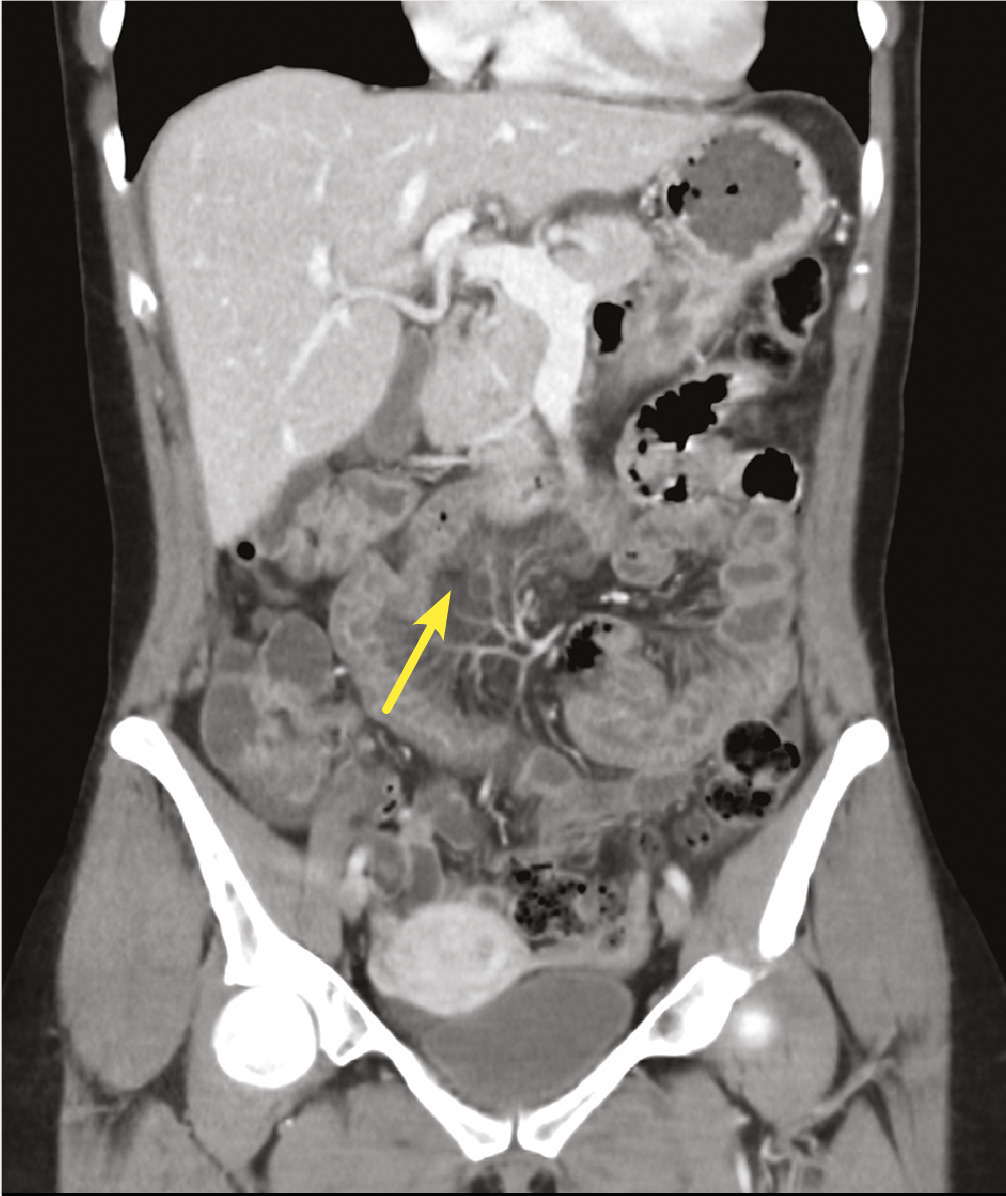

Cette femme de 49 ans consultait aux urgences pour des douleurs abdominales intenses et diffuses depuis 48 heures, sans arrêt des matières ni des gaz et sans vomissements. Cette patiente hypertendue, traitée, signalait la prise de ramipril depuis 48 heures. L’hémogramme montrait une hyperleucocytose à polynucléaires neutrophiles ; la protéine C-réactive était normale. La tomodensitométrie abdominopelvienne (TDM) notait une jéjuno-iléite étendue avec épanchement péritonéal de moyenne abondance sans cause évidente (v. figure ). La patiente était hospitalisée. Un repos digestif et des antalgiques de palier 2 puis 1 permettait une évolution rapidement favorable, la réalimentation à 48 heures, avec reprise du transit digestif et retour à l’état antérieur sans séquelles. Le bilan biologique avec dosage C1 inhibiteur, C3, C4, et ANCA était négatif. L’électrophorèse des protides sériques retrouvait une hypoalbuminémie modérée. La sérologie des Yersinia était négative. Le diagnostic d’angiœdème induit par les inhibiteurs de l’enzyme de conversion (IEC) contre-indiquait définitivement la prescription de cette classe médicamenteuse.